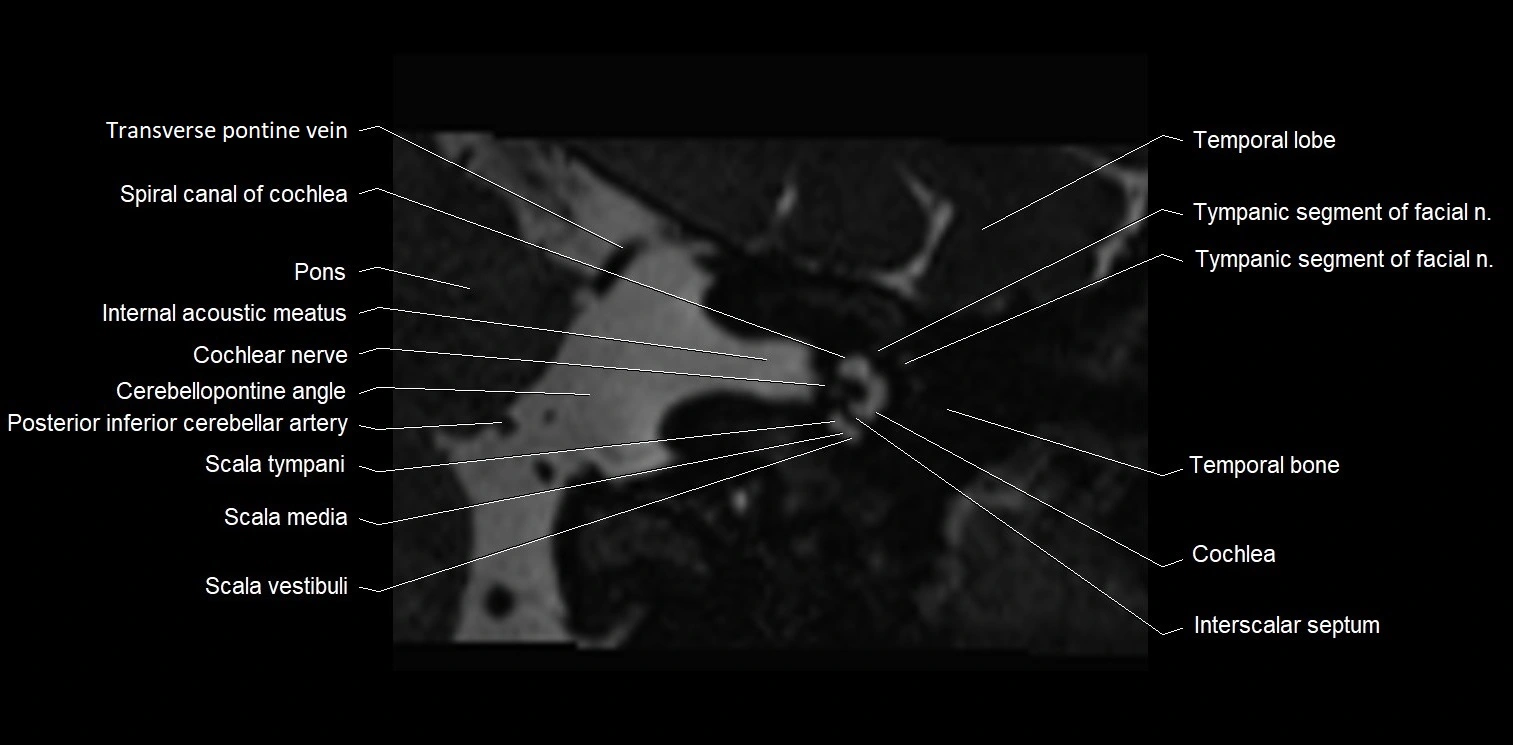

MRI Appearance

• The abducens nerve is a small, thin, linear structure

• Best visualized on high-resolution T2-weighted 3D MRI sequences (e.g., FIESTA or CISS)

• Seen as a hypointense (dark) line running from the brainstem at the pontomedullary junction, traversing the prepontine cistern, and entering Dorello’s canal under the petrosphenoidal ligament, then into the cavernous sinus, and finally the orbit

• May be challenging to visualize in standard MRI due to its small size

• Pathology may be inferred by absence, displacement, or enhancement of the nerve